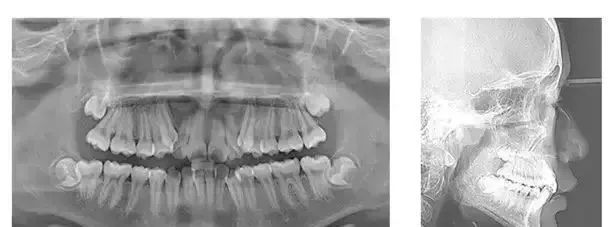

▲

术前X光照

正畸的时间一般在1到2年之间,不过,短短几个月,正畸的效果就可以这么明显!